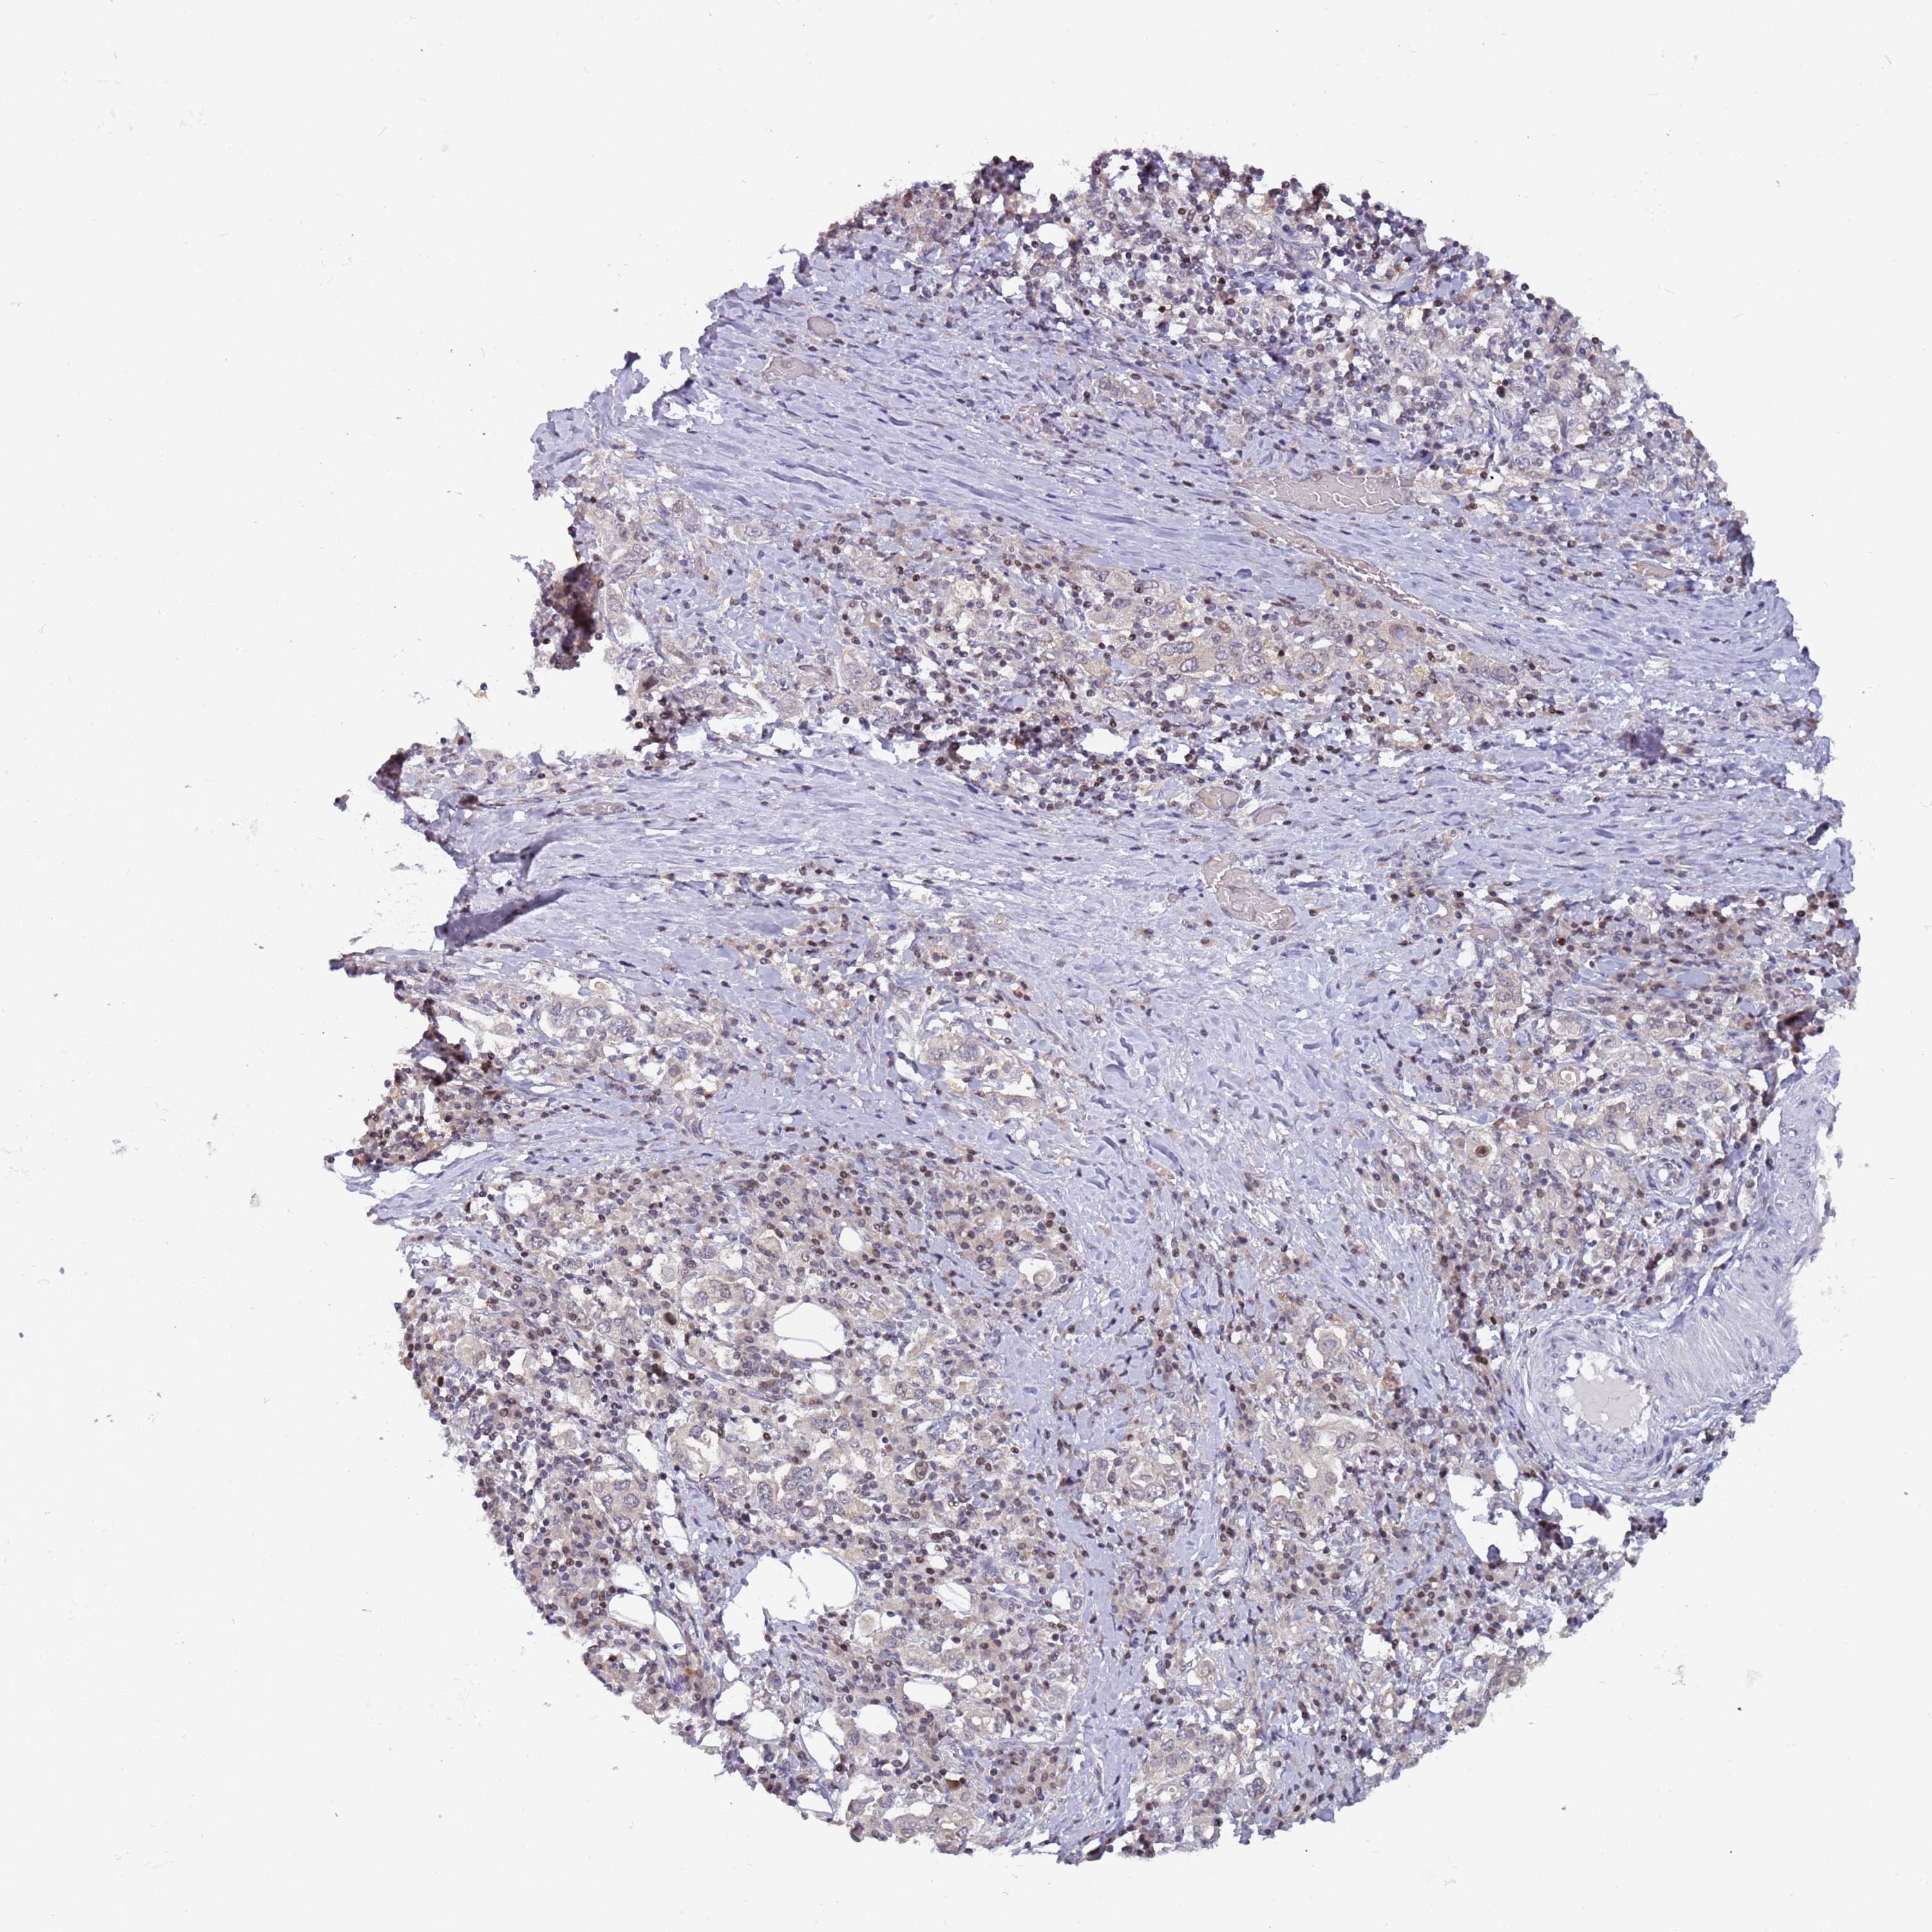

STOMACH CANCER - Protein expressioni

A mouse-over function shows sample information and annotation data. Click on an image to view it in a full screen mode. Samples can be filtered based on level of antibody staining by selecting one or several of the following categories: high, medium, low and not detected. The assay and annotation is described here.

Antibody stainingi

Antibody staining in the annotated cell types in the current human tissue is reported as not detected, low, medium, or high, based on conventional immunohistochemistry profiling in selected tissues. This score is based on the combination of the staining intensity and fraction of stained cells.

Each image is clickable and will lead to virtual microscopy that enables deeper exploration of all samples and also displays staining intensity scores, fraction scores and subcellular localization as well as patient and tissue information for each sample.

Antibody HPA044188

Antibody HPA045619

Antibody HPA045699

Staining

High

Medium

Low

Not detected

Intensity

Strong

Moderate

Weak

Negative

Quantity

>75%

75%-25%

<25%

None

Location

Nuclear

Cytoplasmic/membranous

Cytoplasmic/membranous,nuclear

Adenocarcinoma, NOS